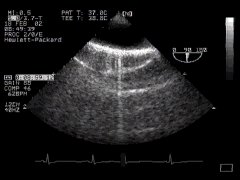

It is easy to imagine the circular image of the descending aorta seen in short axis view when the TEE probe is inserted to about 40cm and turned slightly left. Here it is - 'DESC Aorta SAX':

CLICK FOR VIDEO: descending aorta SAX view